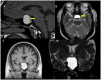

Pituitary apoplexy is a rare syndrome, graded from asymptomatic subclinical apoplexy to a life-threatening condition due to pituitary ischemia or haemorrhage of an enlarged pituitary gland. The risk factors and the molecular underlying mechanisms are yet to be elucidated. We provide an overview of the general concepts, the potential factors associated with pituitary adenoma susceptibility for apoplectic events and the molecular mechanisms that could be involved such as HIF-1α/VEGF pathways and metalloproteinases activation, among others. The knowledge of the molecular mechanisms that could participate in the pathogenesis of pituitary apoplexy is crucial to advancement in the identification of future diagnostic tools and therapeutic targets in this rare but sometimes fatal condition.